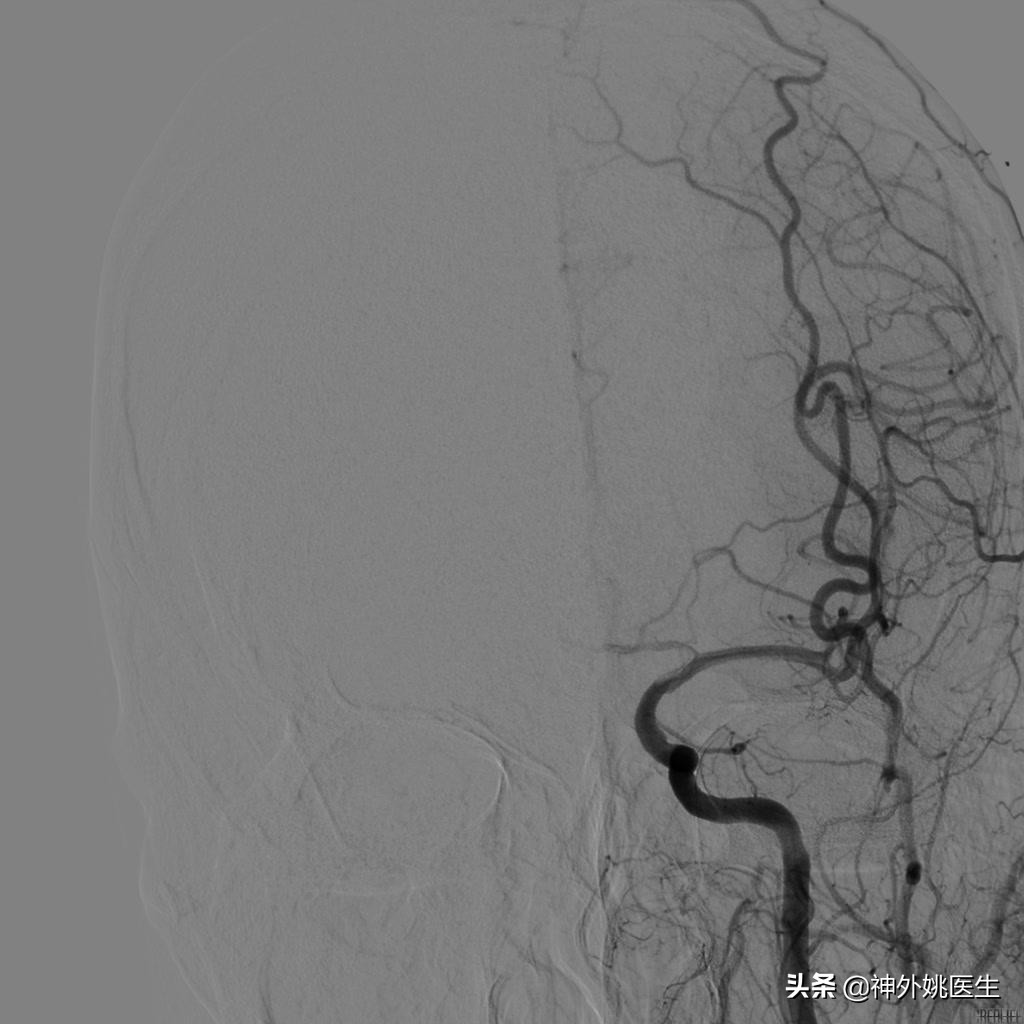

术前DSA检查:(图3-6)

图5 左侧颈动脉造影示左侧大脑前动脉显影欠佳。

图6 椎基底动脉造影示左侧后交通动脉开放,左侧大脑中动脉显影。